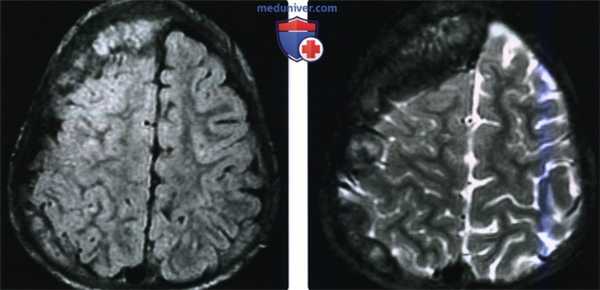

(Слева) При аксиальной МРТ FLAIR у пациента с экстрадуральной метастатической нейробластомой визуализируется опухоль с неоднородным сигналом. Несмотря на объемное воздействие опухоли, выраженное в значительной степени, со стороны вещества мозга, прилежащего к ней, определяются лишь легкие реактивные изменения.

(Справа) При аксиальной МРТ Т2 ВИ у этого же пациента визуализируется метастатическая нейробластома с сигналом неравномерной интенсивности (в том числе гипоинтенсивным). Гипоинтенсивный сигнал на Т2 ВИ типичен для опухолей с высокой целлюлярностью и высоким ядерно-цитоплазматическим отношением.